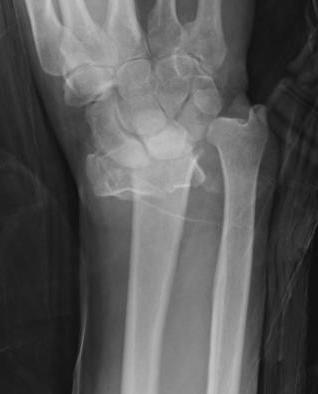

Distal Radius Angles

- radial volar tilt 11°

- radial inclination  22°

- radius is 11 mm longer than ulna

- ulna variance 2mm positive on average

Distal Radius NormalNormal Radial InclinationNormal Radial Length